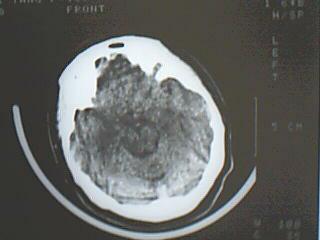

以下是引用liyf在2008-8-14 20:00:00的发言:[br]右侧基底节区脑出血。